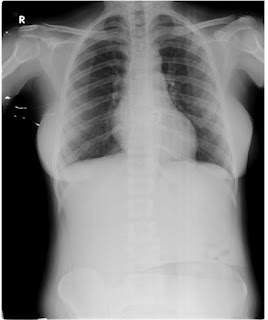

Respiratory system

Inspection

Chest is bilaterally symmetrical

The trachea appears to be in centre

Chest moves equally with respiration on both sides

No dilated veins, scars or sinuses are seen

Palpation-

Trachea is felt in midline

Chest moves equally on both sides on respiration

Tactile vocal fremitus- appreciated

Percussion-

The areas percussed include the supraclavicular, infraclavicular, mammary, axillary, infraaxillary, suprascapular, infrascapular areas.

They are all resonant.

Auscultation-

Normal vesicular breath sounds are heard

No adventitious sounds